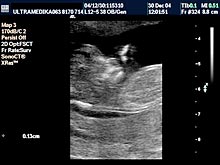

Jedna trudnoća se ne može smatrati vitalnom ako se ne registruje srčana radnja ploda. Čak šta više u zavisnosti od veličine ploda srčana radnja je različite učestalosti. Obaveza je doktora da M-modom tačno izmeri frekvencu srčane radnje. Usporen srčani rad u odnosu na starost trudnoće obično predstavlja loš prognostički znak za vitalnost trudnoće!